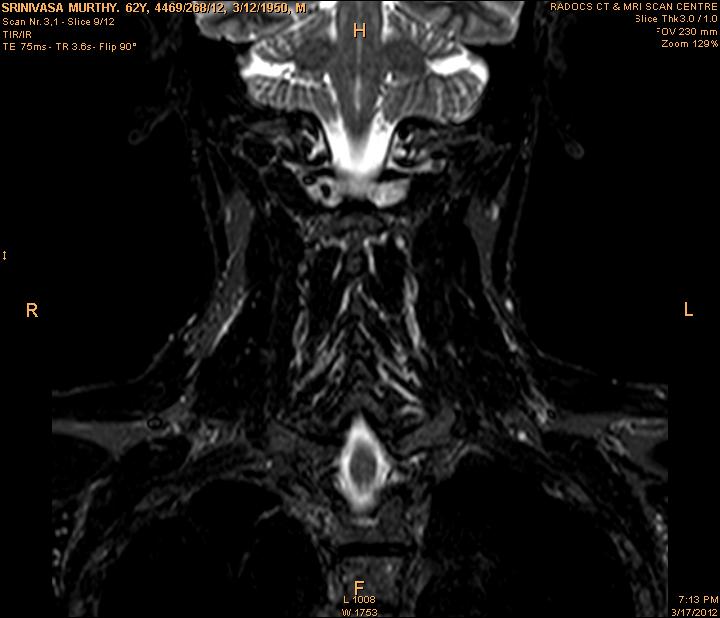

In order to show the proposed method in more detail, the algorithm is tested with other test images. The first row of Fig. 6 shows the original MRI image of thoracic spine with different views. The second row of Fig. 6 shows the same image enhanced using histogram equalization. Third row of Fig. 6 presents the MSR based enhancement scheme. Fourth row of Fig. 6 indicates Chao’s method of image enhancement. Finally, the reconstructed images using the proposed method is shown in fifth row of Fig. 6. Again, it can be seen from the results presented that the image enhancement using the proposed method is superior compared to other methods. This is evident from the image quality assessment presented in Table 1 using AWE and DWE.